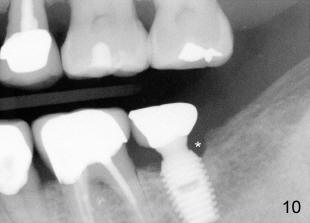

The patient has complained discomfort since cementation. Fig.9,10 X-ray was taken 11 months post-cementation, showing bone resorption, particularly in the distal aspect of the crest (*). At that time, there was food impaction between #18 and 19. Pick-up impression was taken to modify contact area of #18.